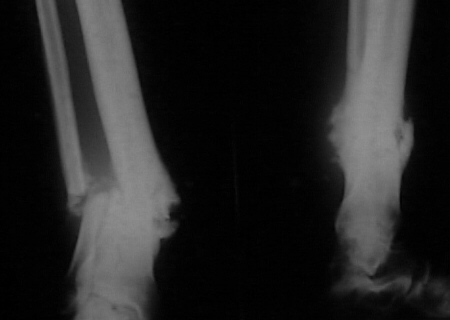

Nail arthrodesis for failed pilon fracture is good solution.

My example

Michael Berenstein